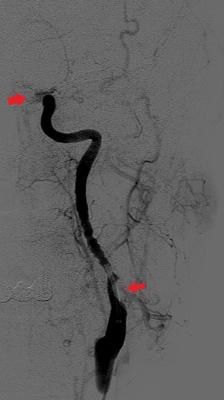

文章图片

颈动脉造影:血管近端可见充盈缺损(下箭头),提示颈动脉夹层,远端血管(上箭头)因血栓堵塞而不显影。